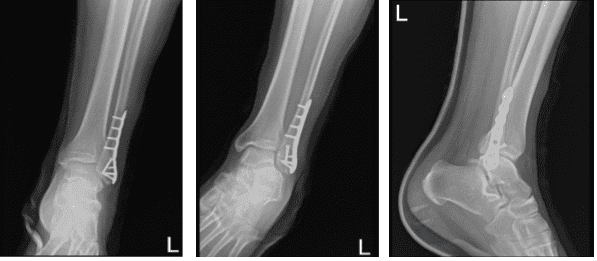

Una semana después de la cirugía, la paciente fue enviada a una radiografía. La PA, lateral y oblicua. No hay exámenes previos disponibles para comparación. El examen se realiza a través de un molde superpuesto que oculta parcialmente detalles óseos. El paciente está en estado tras fractura distal del peroné ORIF.

La línea de fractura apenas es visible. El equipo quirúrgico está intacto. Los aspectos visualizados del astrágalo izquierdo, el calcáneo y los huesos tarsianos muestran márgenes corticales intactos sin evidencia de fractura aguda. No hay cambios degenerativos significativos. La mortaja de tobillo está bien mantenida.

No hay hinchazón apreciable de tejidos blandos. No hay espolón plantar calcáneo. Da la impresión de que no existen exámenes previos disponibles para comparar.

Tras semanas, el paciente volvió a la consulta para su revisión de seguimiento, con una radiografía del tobillo para revisión. Niega fiebre, escalofríos, dolor y es WBAT con botas, sin muletas. Se revisaron y discutieron radiografías, hay una fractura quirúrgicamente tratada en el peroné distal izquierdo.

Se visualiza una línea de fractura tenue, la tibia distal izquierda es poco destacable y los aspectos visualizados del astrágego izquierdo, el calcáneo y los huesos tarsianos muestran márgenes corticales intactos sin evidencia de fractura aguda.

La mortaisa del tobillo está bien mantenida, sin embargo, hay una leve hinchazón de tejidos blandos lateralmente y no hay espolón plantar calcáneo.